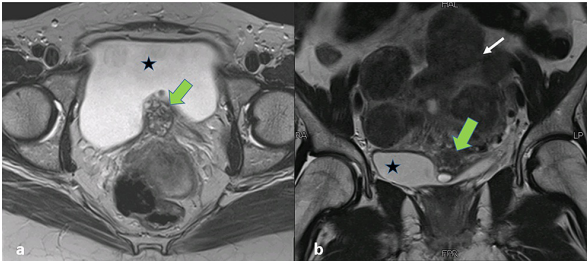

骨盆MRI显示增大的子宫,有多个子宫肌瘤和沿膀胱后壁的不规则混合信号强度肿块。该病变表现为膀胱内延伸,向后与子宫接触,脂肪平面不明显(图2)。经仔细检查,发现该病变引起了可能侵犯肌肉的外在印象。它的颅尾、AP和横向尺寸为36 x 29 x 21 mm,外观提示膀胱生长。然而,该病变的信号特征是出血性病变的典型特征,在T2加权序列上返回异质性低信号(图2),T1加权序列上的异质高信号,伴有斑片状对比增强(图2)(图3)和焦点扩散限制(图4)。鉴于患者的病史,MRI检查结果与膀胱子宫内膜异位症一致。

图2. 骨盆MRI图像。(a) 轴向T2加权图像和 (b) 冠状T2加权图像显示沿膀胱底部(星形标志)的T2低信号病变(绿色箭头),轮廓异常。子宫肌瘤显示在冠状位(白色箭头)